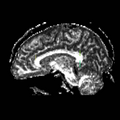

File:Cing1ROIs.png

Cing1ROIs.png (512 × 512 pixels, file size: 104 KB, MIME type: image/png)